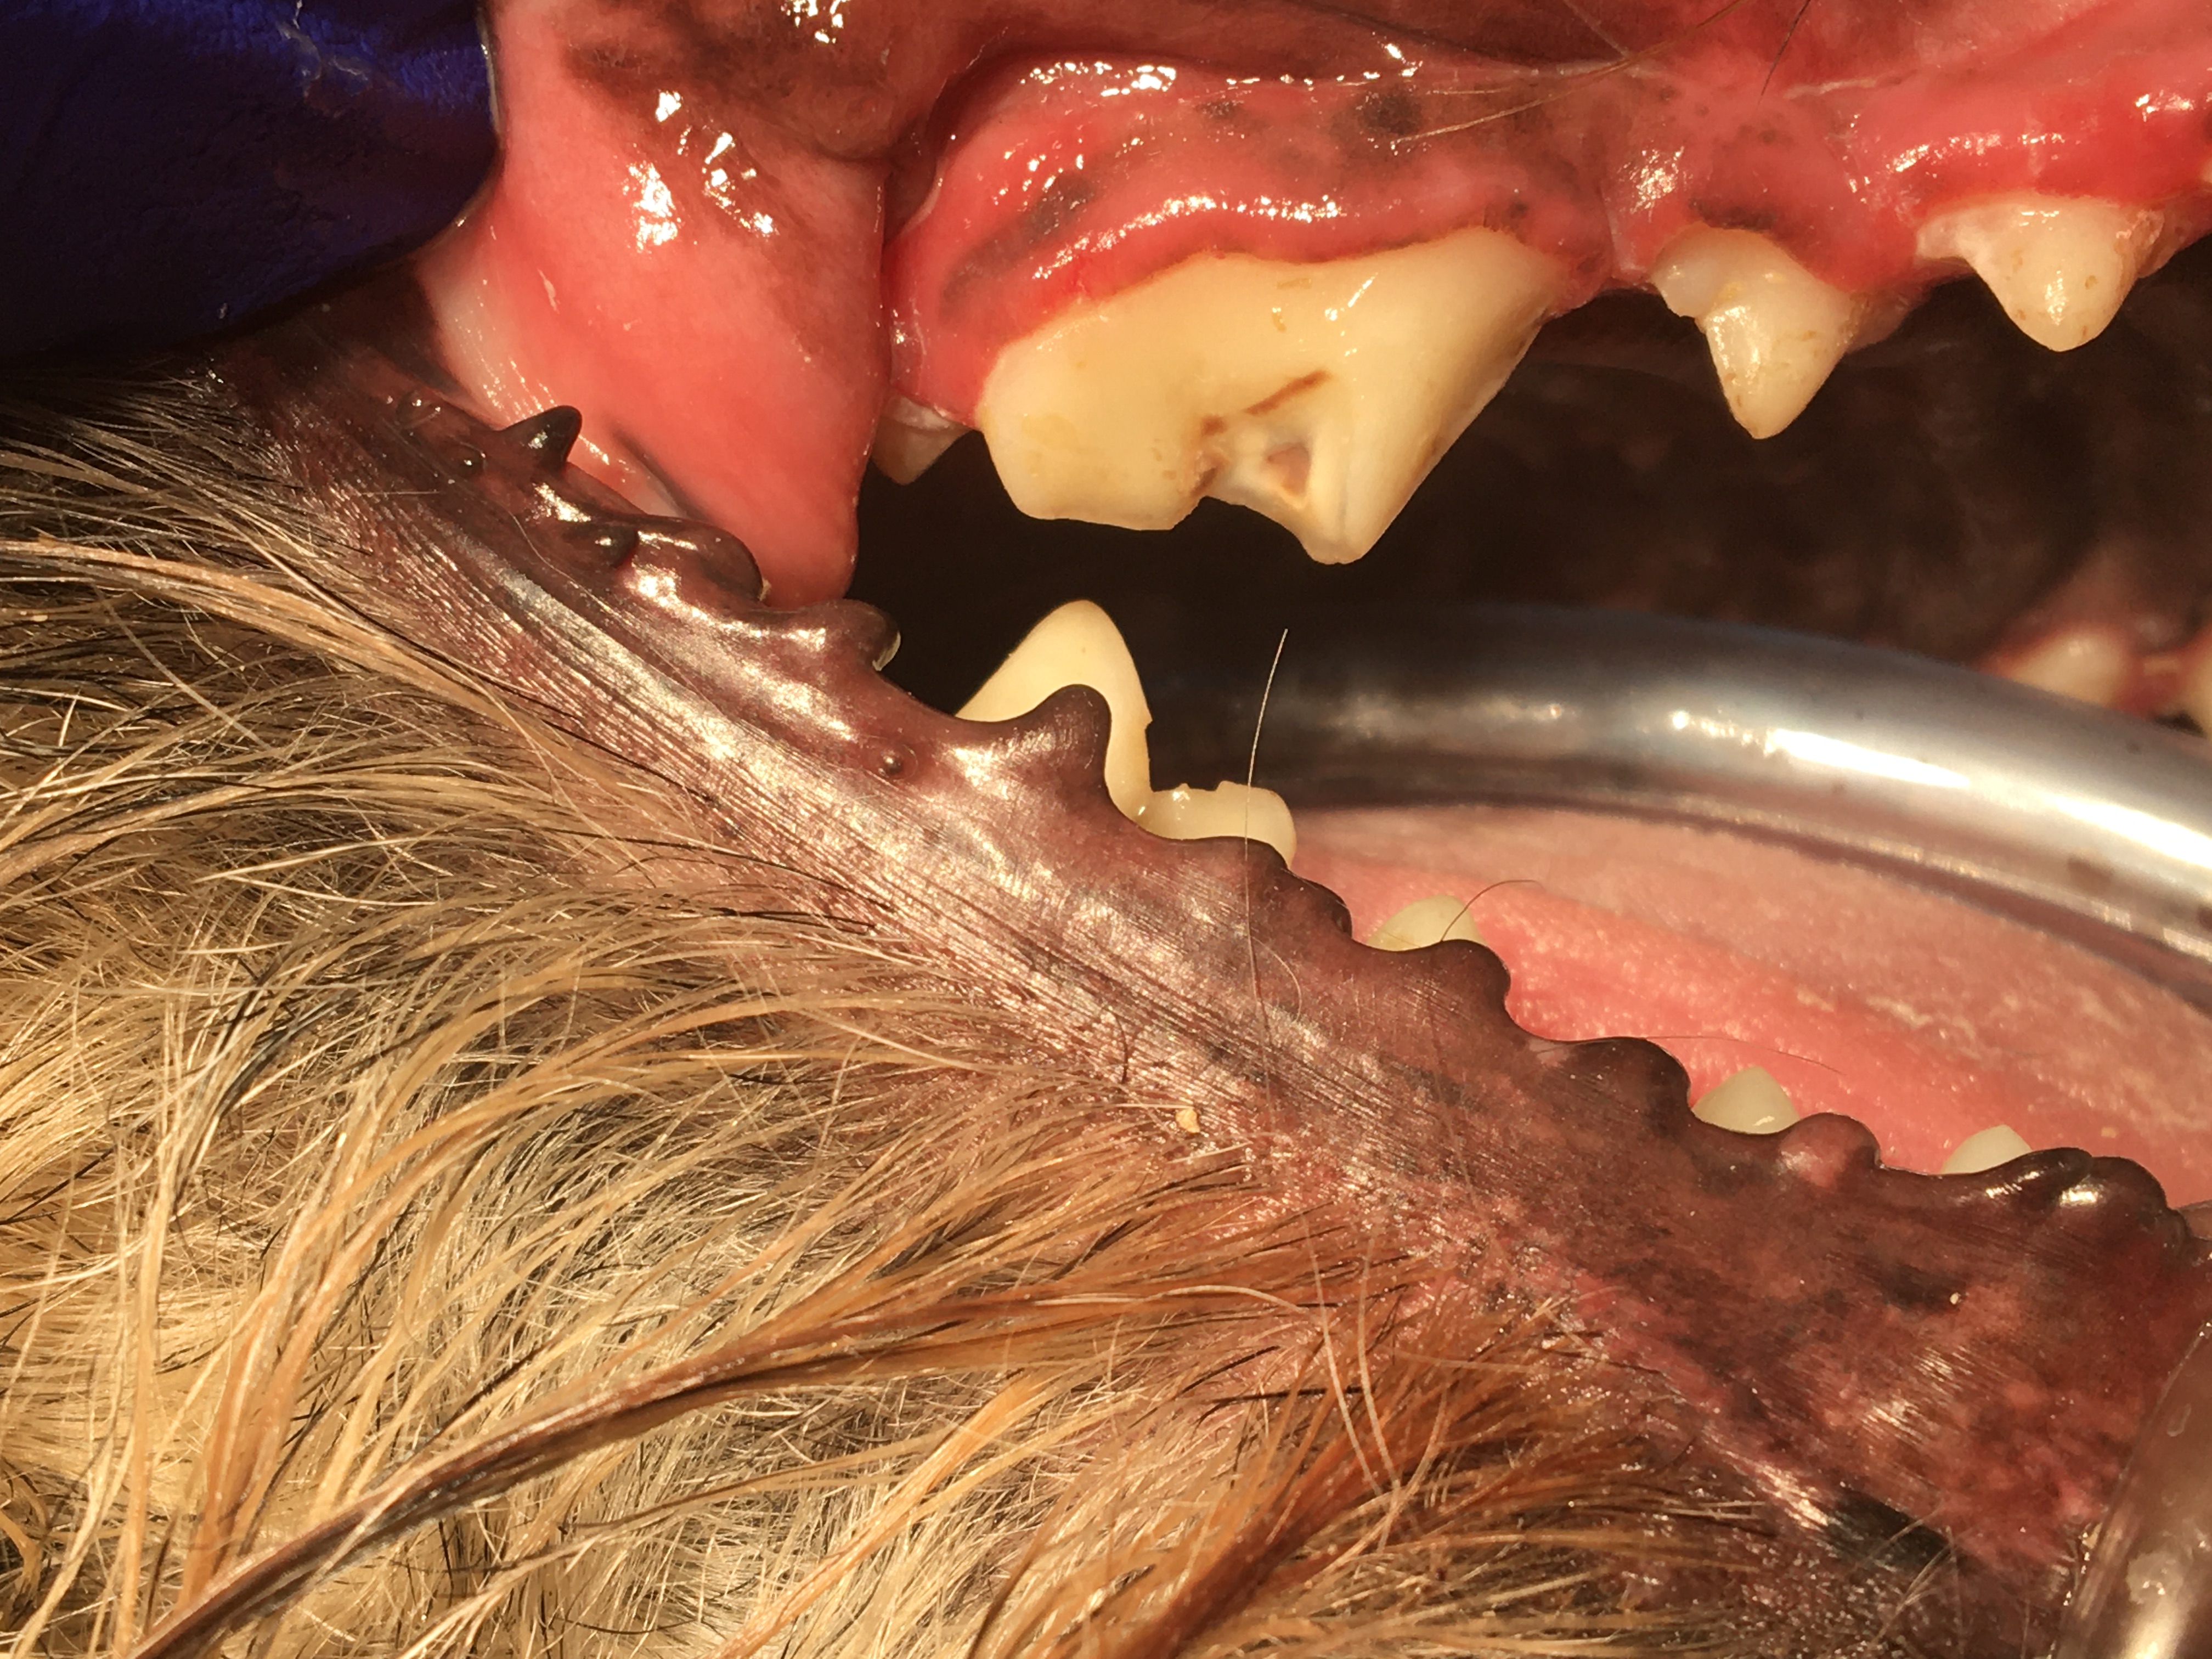

Feline Odontoclastic Resorptive Lesions

Felines exhibit a unique erosion at the cervical area called Feline Odontic Resorptive Lesions. These lesions appear to be associated with localized gingivitis. Many people have tried to explain why these lesions develop, however no one has come up with a definitive etiology.

I have restored FORL lesions with silver amalgam with excellent long term effect in multiple feline species. The lesions have ceased to enlarge. Restoration attempts with composite resin will fail, erosion will continue. Regrettably, most dentists and veterinary dentists will no longer have silver amalgam and the necessary instruments available to use it.

In personal conversations with Dr. Thomas Clark at Louisville Zoo I learned that he also has had success with silver amalgam. The lesion must be prepared with inverted cone burs to establish mechanical retention. These restorations have held up without failure for many years, see photos.